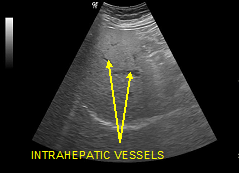

The fatty infiltration of the liver is shown on ultrasound with significantly increased echogenicity "bright liver", in comparison with the right kidney cortex (Figure 1). Normally, the liver and the renal cortex have similar echogenicity, relative to the parenchyma of the pancreas and the spleen. The maximum diameter of the liver in the midclavicular line (MCL) was increased, right lobe>15 cm (Figure 5). Also significant features are the absence of mass effect on intrahepatic vasculature (Figure 6) as well as the poor visualization of the deep parts of the liver (Figure 7), due to decreased permeability of the acoustic beam. A focal or diffuse morphology has been shown to increase the echogenicity of the fatty liver. Differential diagnosis is caused by focal fat infiltration (Figure 8), which has a geographic distribution. In this case, hypoechoic areas correspond to normal hepatic parenchyma on fatty infiltration sites, whereas, normal parenchyma islets can easily be identified due to their typical positions, in front of the right branch of the portal vein, its division, around the area of the gallbladder and the caudate lobe.9−13

Figure 6 Deafness of intrahepatic vessels in fatty infiltration.